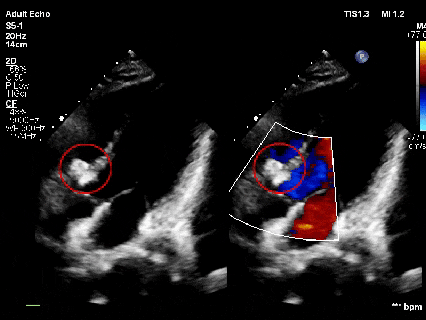

释放后超声

超声下可见室水平和房水平都无残余分流

心脏彩超:心脏超声下可见两个封堵器双盘稳固夹持,无残余分流;

术后1个月心脏超声,房室水平皆无残余分流